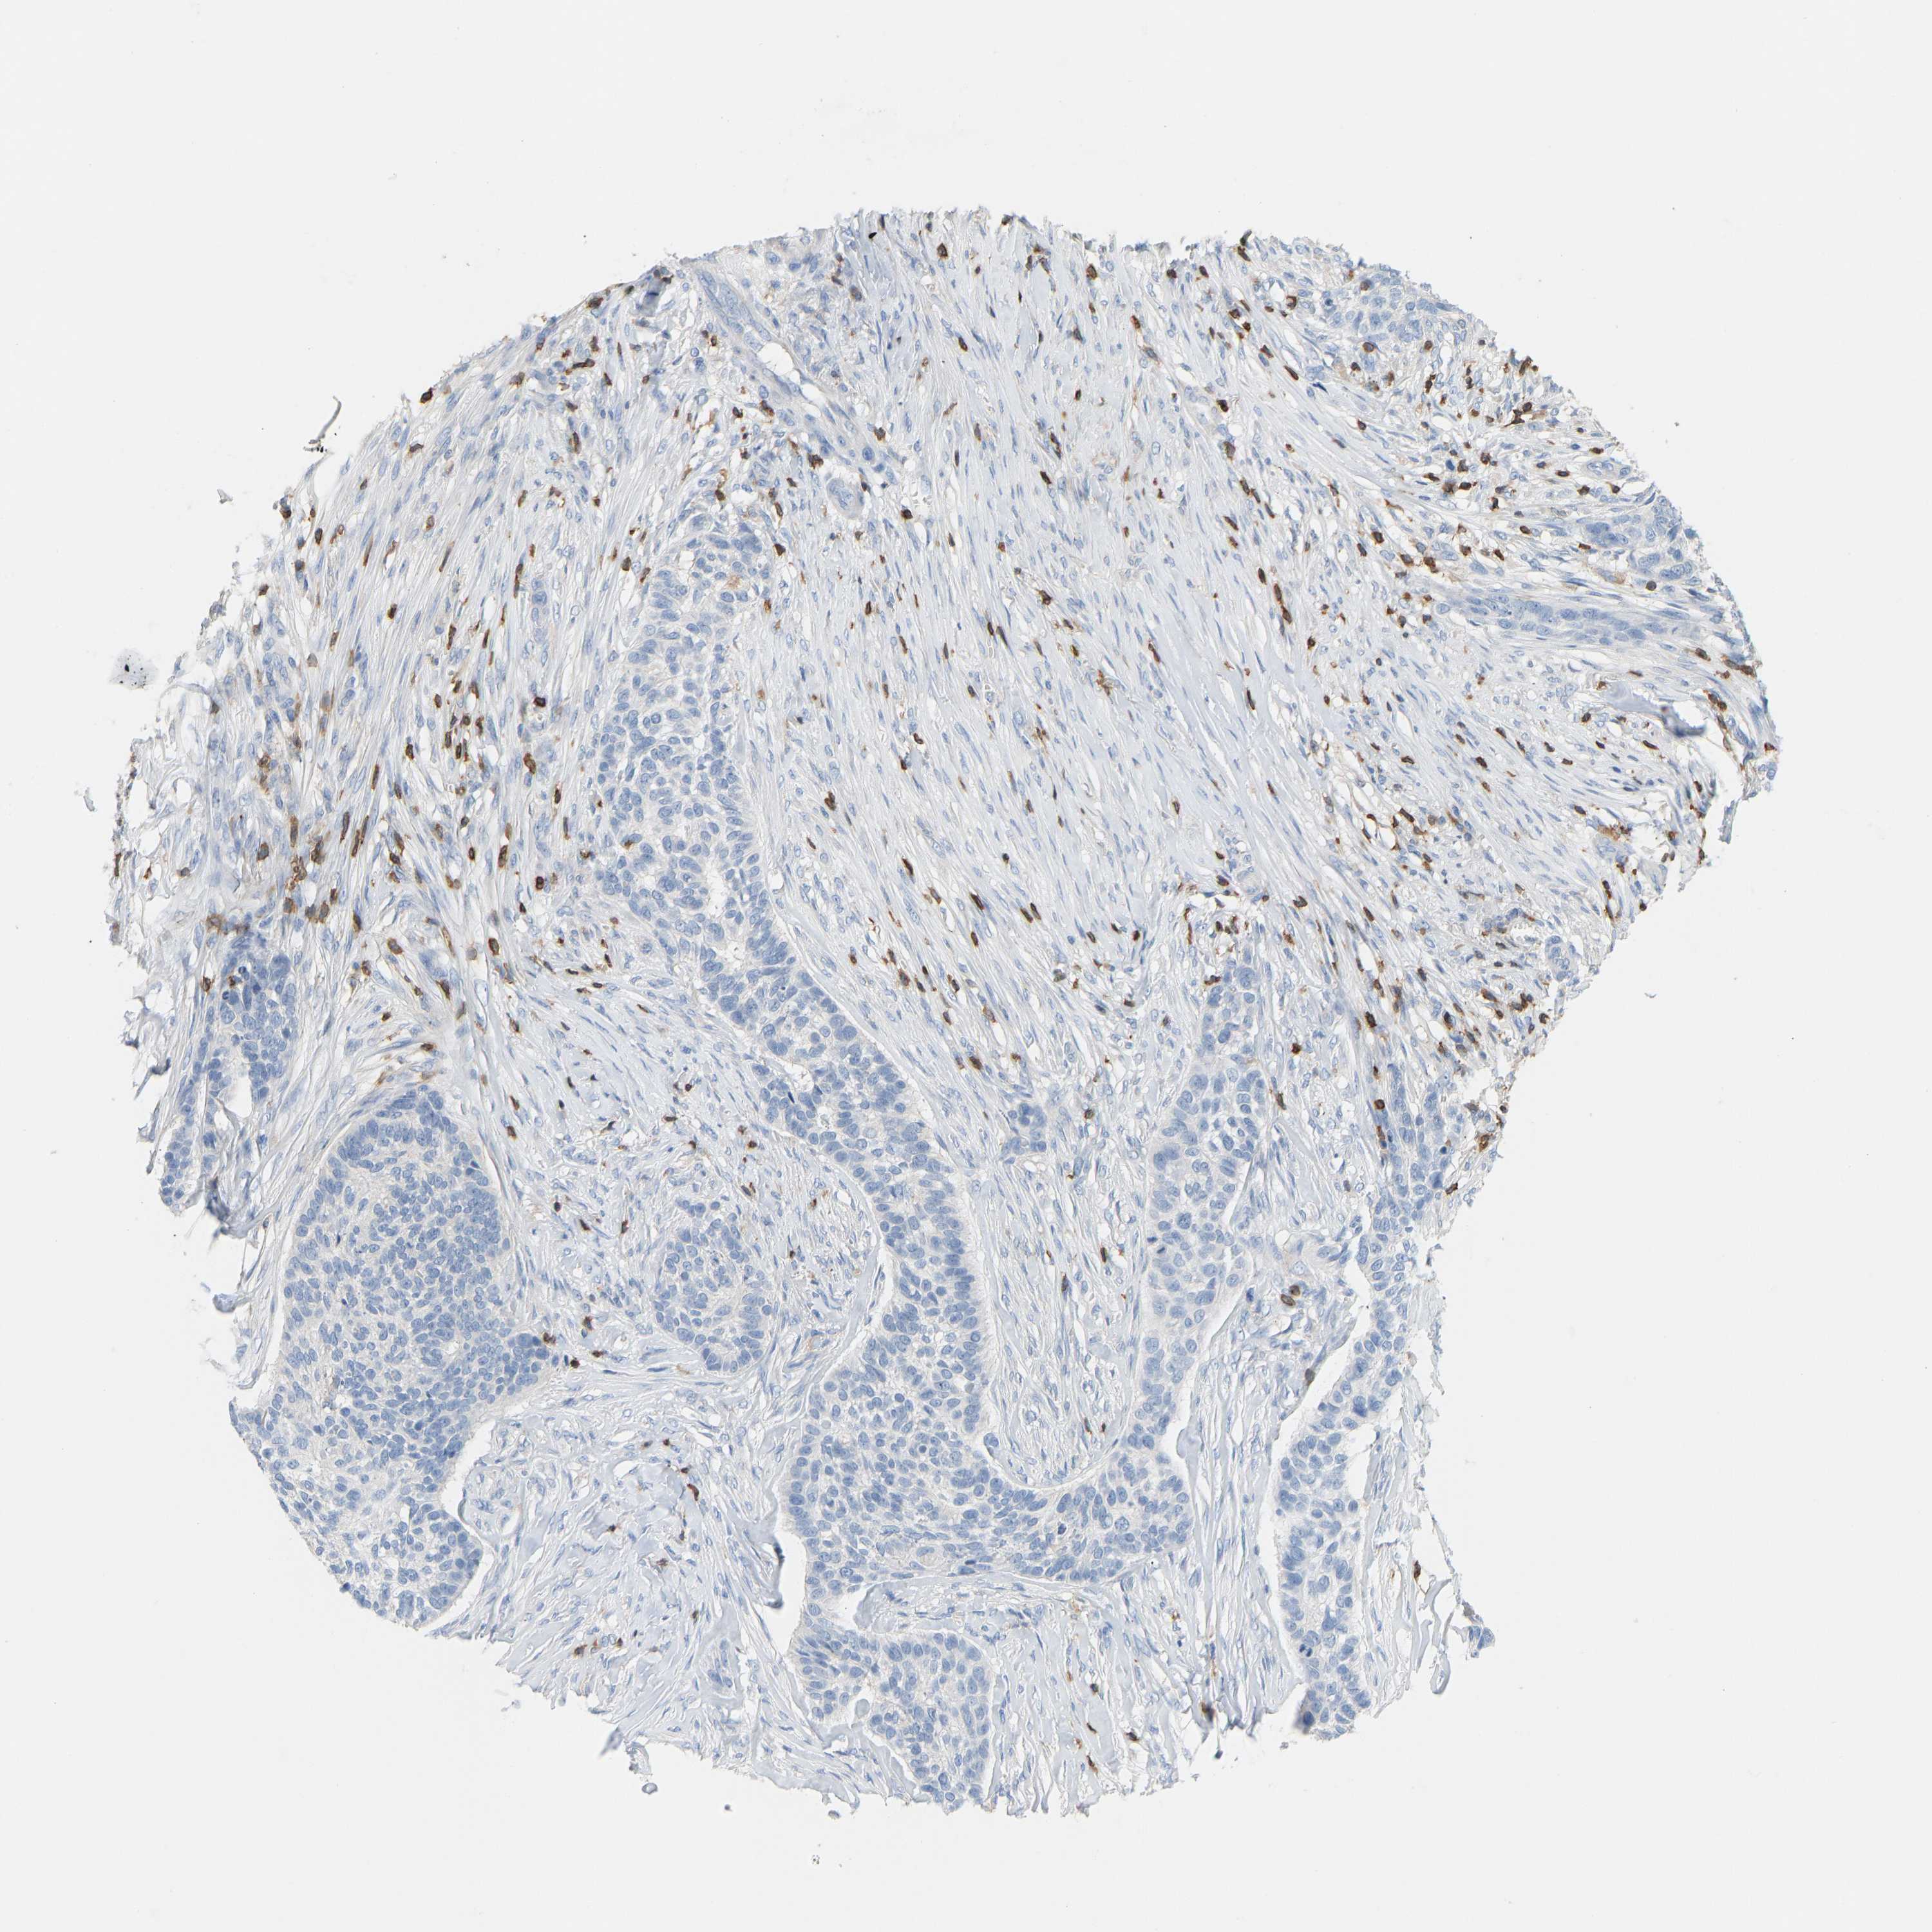

SKIN CANCER - Protein expressioni

A mouse-over function shows sample information and annotation data. Click on an image to view it in a full screen mode. Samples can be filtered based on level of antibody staining by selecting one or several of the following categories: high, medium, low and not detected. The assay and annotation is described here.

Each image is clickable and will lead to virtual microscopy that enables deeper exploration of all samples and also displays staining intensity scores, fraction scores and subcellular localization as well as patient and tissue information for each sample.

Antibody HPA018849

Basal cell carcinoma